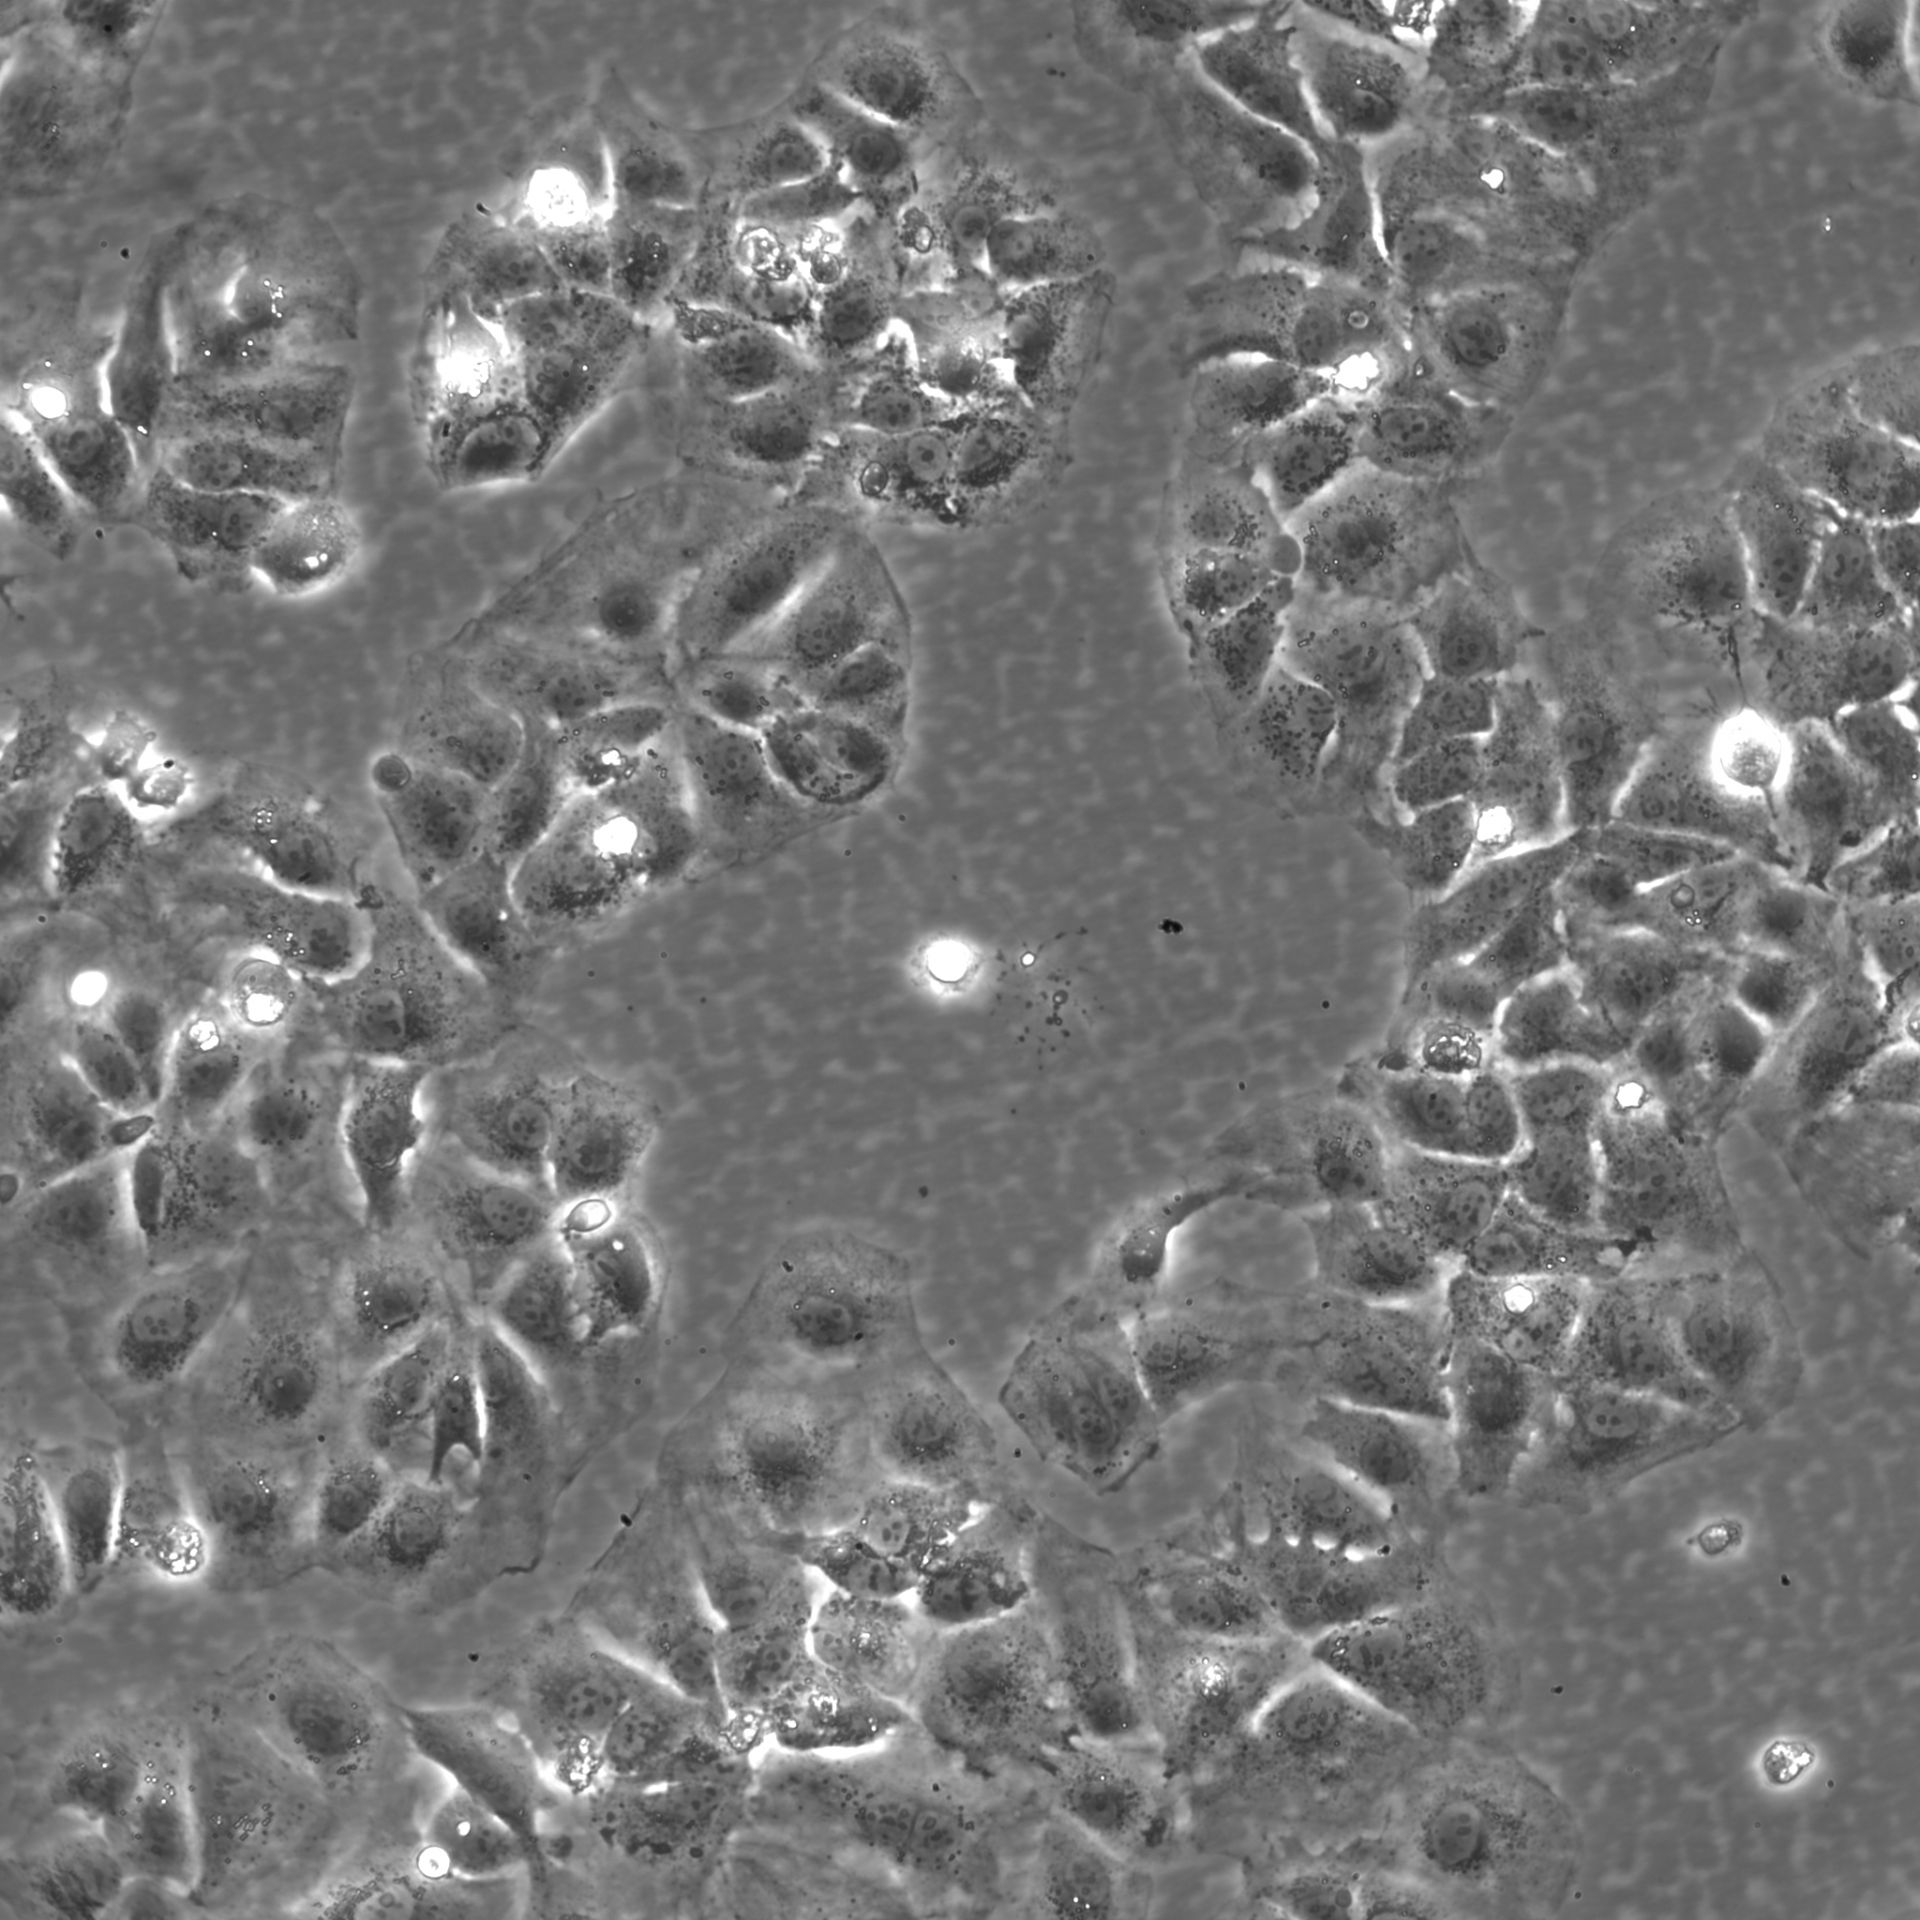

Morphology: Epithelial-like

Growth Properties: Adherent

Description: HuH7 was established in 1982 by Nakabayashi et al. from a 57-year-old Japanese male with well differentiated hepatocellular carcinoma.